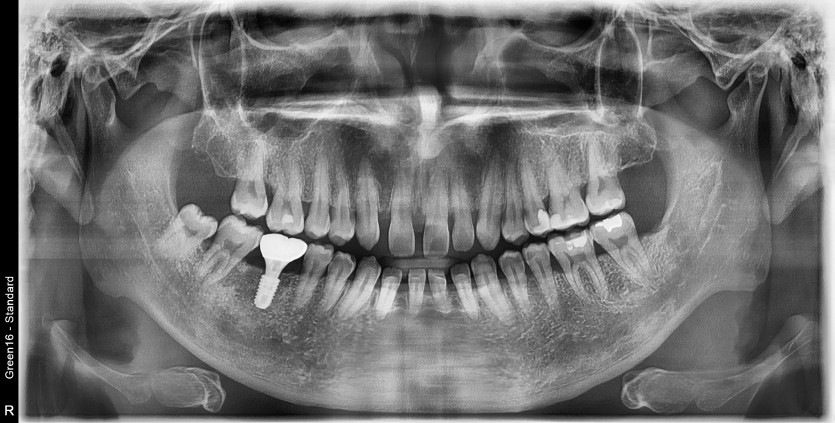

#48 사랑니 발치

구강 외과 전문의가 당일 발치했습니다.